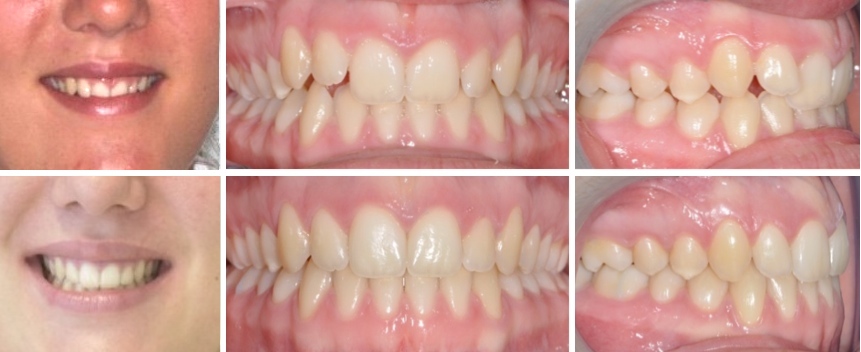

Fall 2: Offener Biss und Engstände

Therapie: Vollfixe Spange und Chirurgie